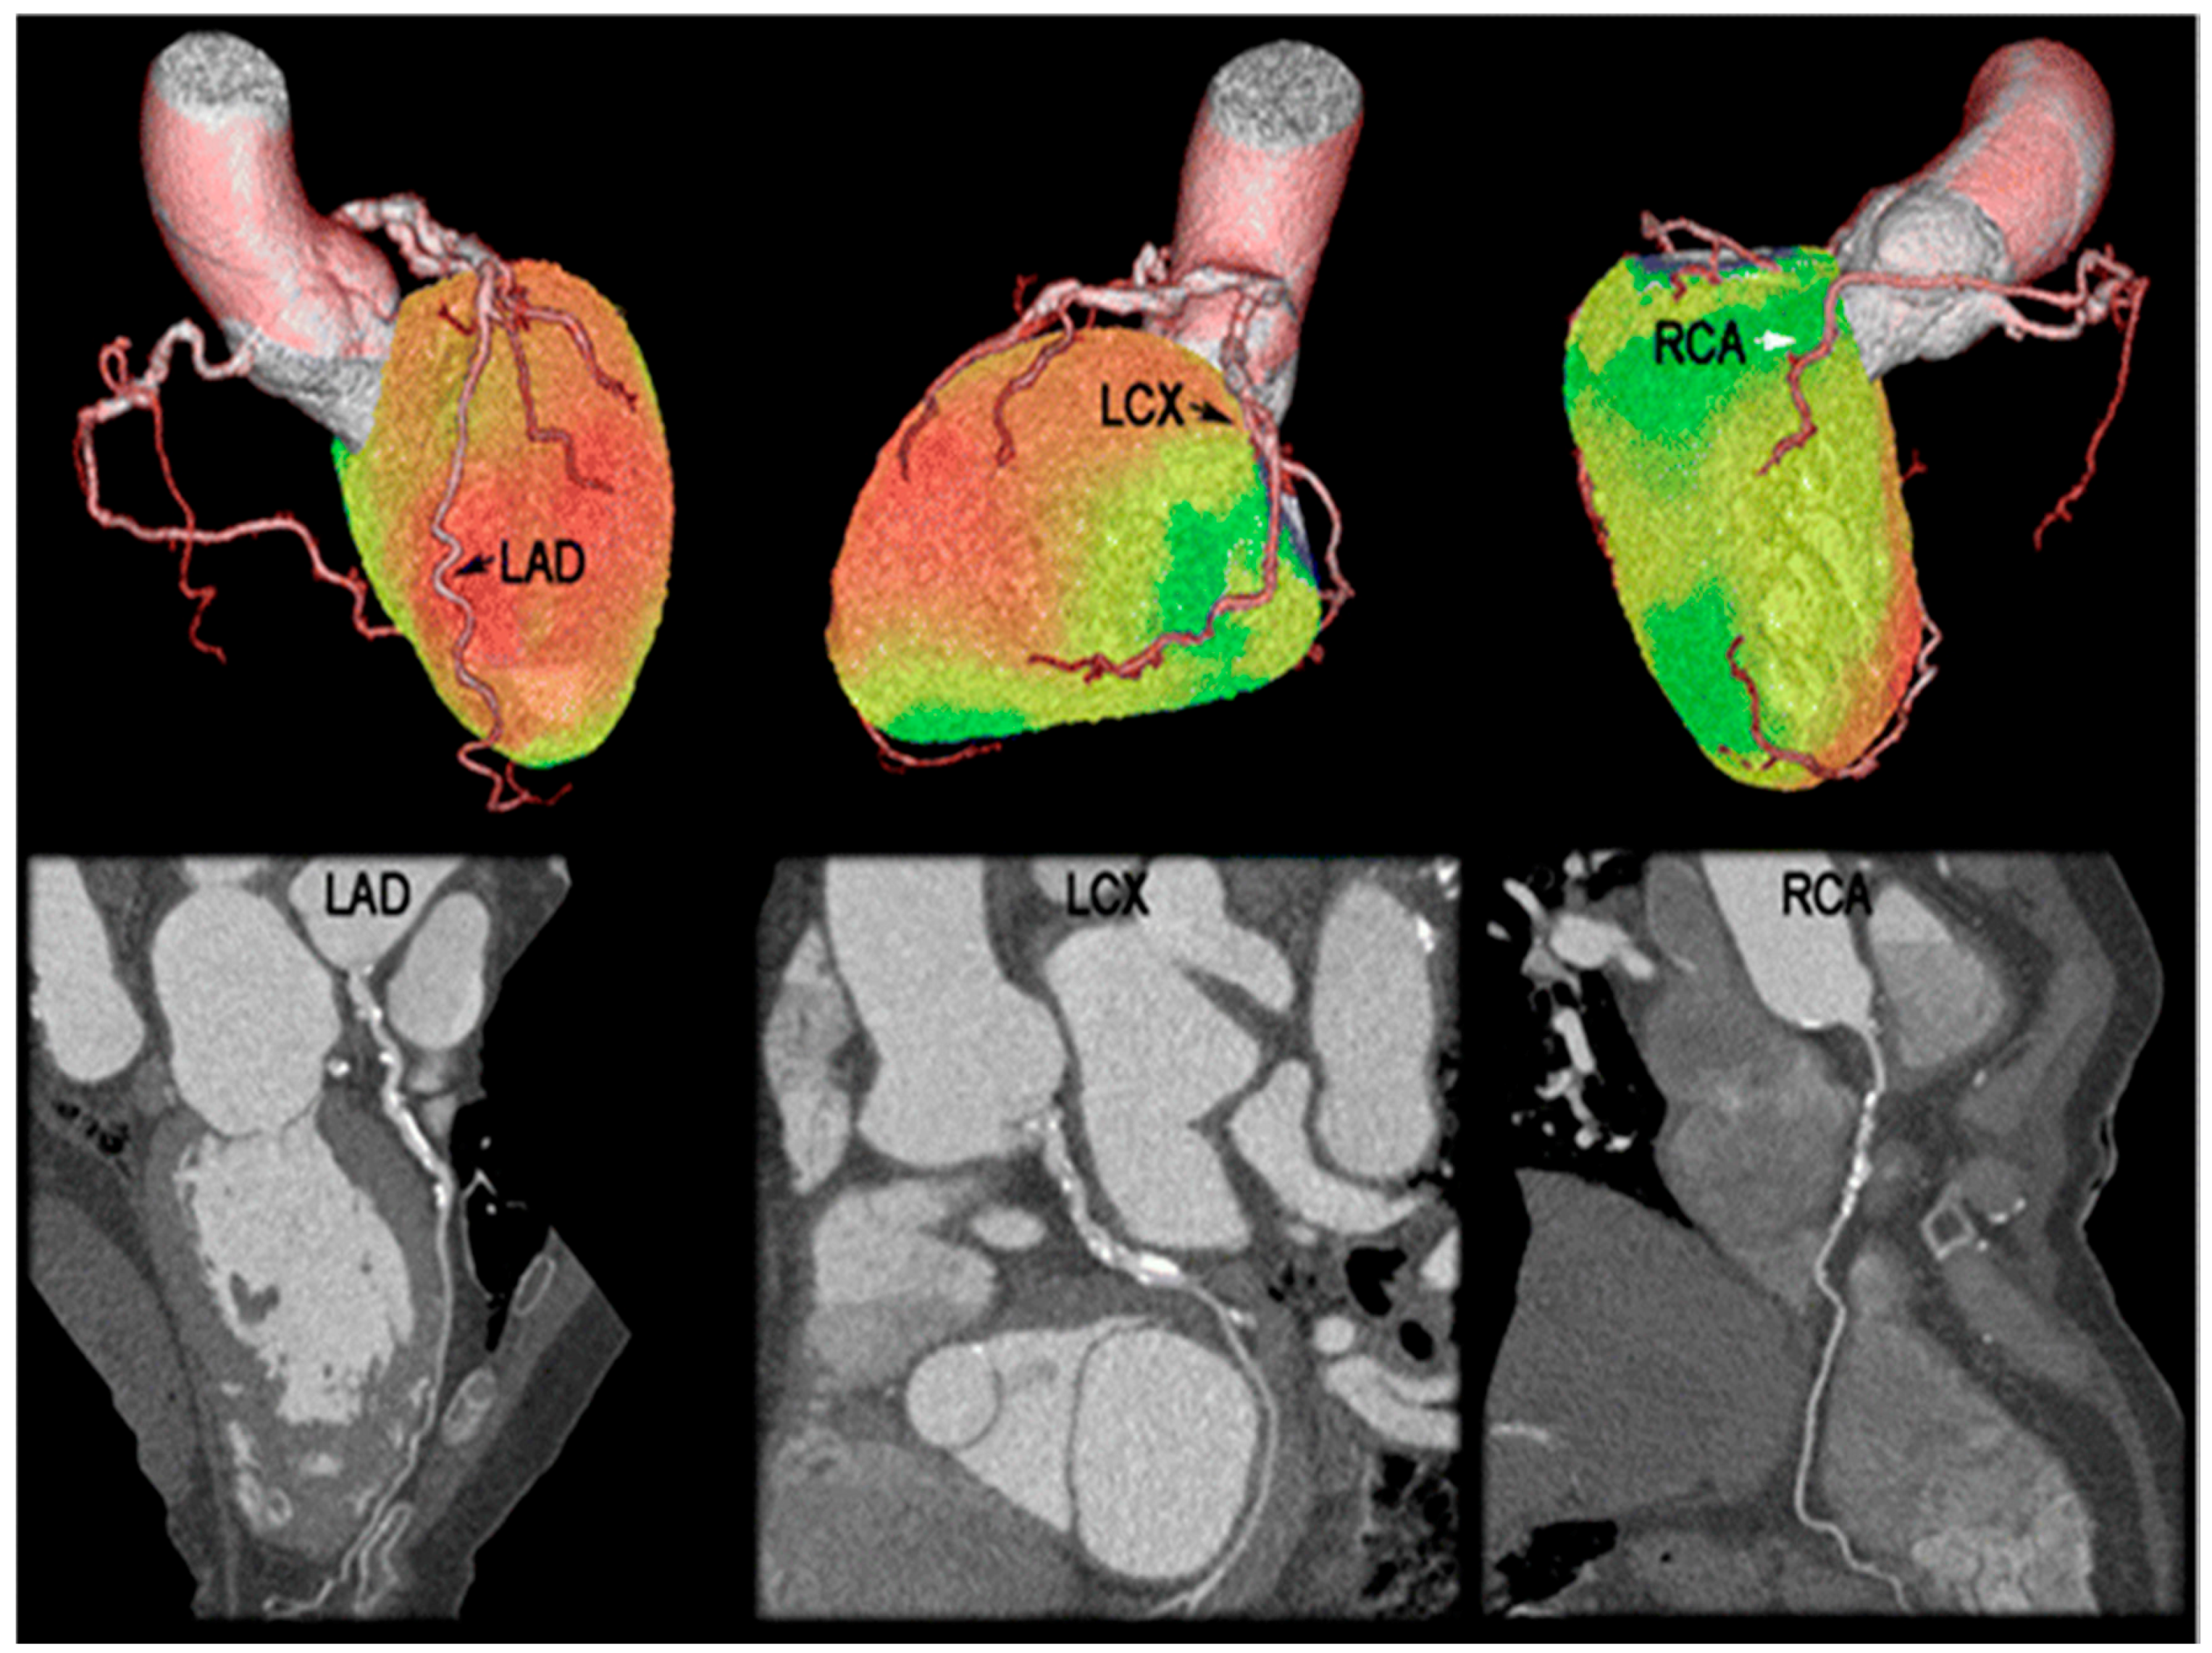

- Cheng, V.Y.; Slomka, P.J.; le Meunier, L.; Tamarappoo, B.K.; Nakazato, R.; Dey, D.; Berman, D.S. Coronary arterial 18F-FDG Uptake by fusion of PET and coronary ct angiography at sites of percutaneous stenting for acute myocardial infarction and stable coronary artery disease. J. Nucl. Med. 2012, 53, 575–583. [Google Scholar] [CrossRef] [PubMed]